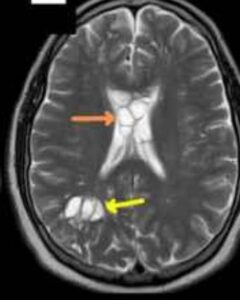

Potrivit medicilor, suspiciunea a apărut după ce durerea de cap s-a intensificat iar tratamentele uzuale nu și-au mai făcut efectul. O serie de tomografii cerebrale a relevat imagini sugestive pentru prezența unor formațiuni parazitare, ceea ce a condus la stabilirea diagnosticului de cisticercoză. Afecțiunea este rară, dar bine documentată: larvele de tenie pot migra și se pot fixa în diverse țesuturi ale corpului, inclusiv în creier.

Un bărbat de 52 de ani din Statele Unite a ajuns la spital după ce migrenele sale, pe care le gestiona de obicei cu analgezice, au devenit brusc imposibil de suportat. Investigațiile imagistice i-au schimbat viața: medicii au identificat în creier leziuni compatibile cu ouă de tenie, diagnosticul fiind cisticercoză — o infecție cauzată de larvele acestui parazit care pot ajunge și în țesutul nervos.